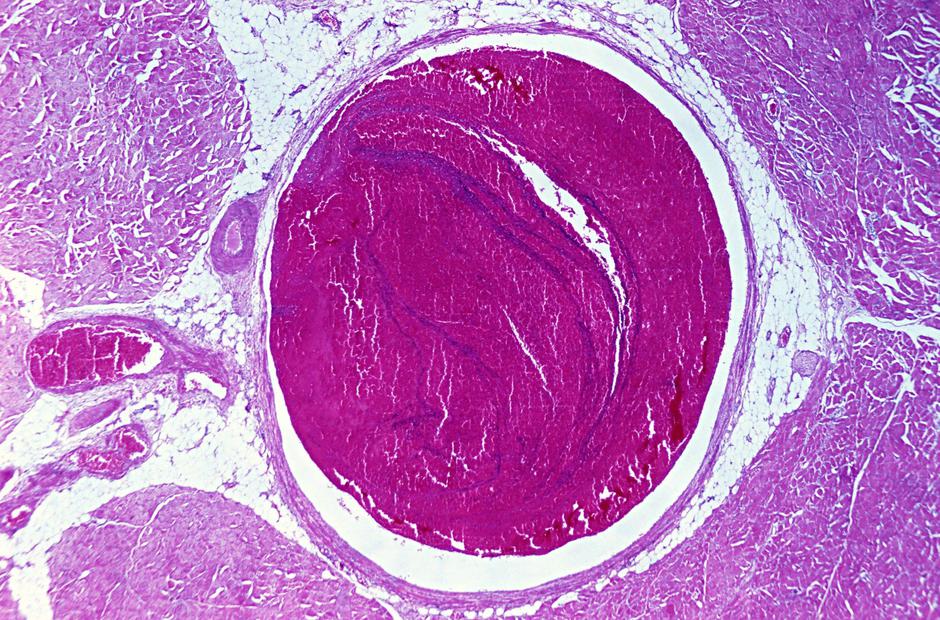

Tromboza pomeni zamašitev arterije (arterijska tromboza) ali vene (venska tromboza) s krvnim strdkom: "Venska tromboza je tista, ki je v javnosti najmanj prepoznavna. Nastane v venah, najpogosteje v venah spodnjih okončin in v medenici. Poglavitna nevarnost je, da se strdek od tam odtrga ali potuje naprej do pljuč, kjer zamaši pljučne žile," je pojasnila Dr. Tjaša Vižintin Cuderman z Interne klinike UKC Ljubljana.

Tromboza | Avtor: Profimedias Profimedias